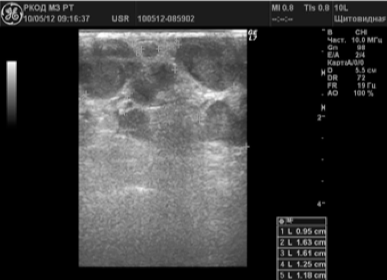

У 127 (83,6%) пациентов при проведении ультразвуковых исследований были выявлены подозрительные на злокачественное поражение лимфатические узлы. В 69 (45,4%) случаях подозревалась злокачественная лимфома. Визуализировались множественные увеличенные периферические лимфатические узлы нескольких зон, многие из них были спаяны между собой (рис. 2).

Рисунок 2.

Лимфоузлы шеи при лимфогранулематозе

При раковой опухоли лимфатической системы чаще всего бывает поражен не один, а группа лимфоузлов в нескольких областях. Они увеличиваются в размерах и визуализируются на экране в виде новообразования из слившихся лимфоузлов между собой или с близлежащими тканями. Контуры лимфоузлов чаще остаются четкими. Отмечается разрастание дополнительных кровеносных сосудов (рис.2)